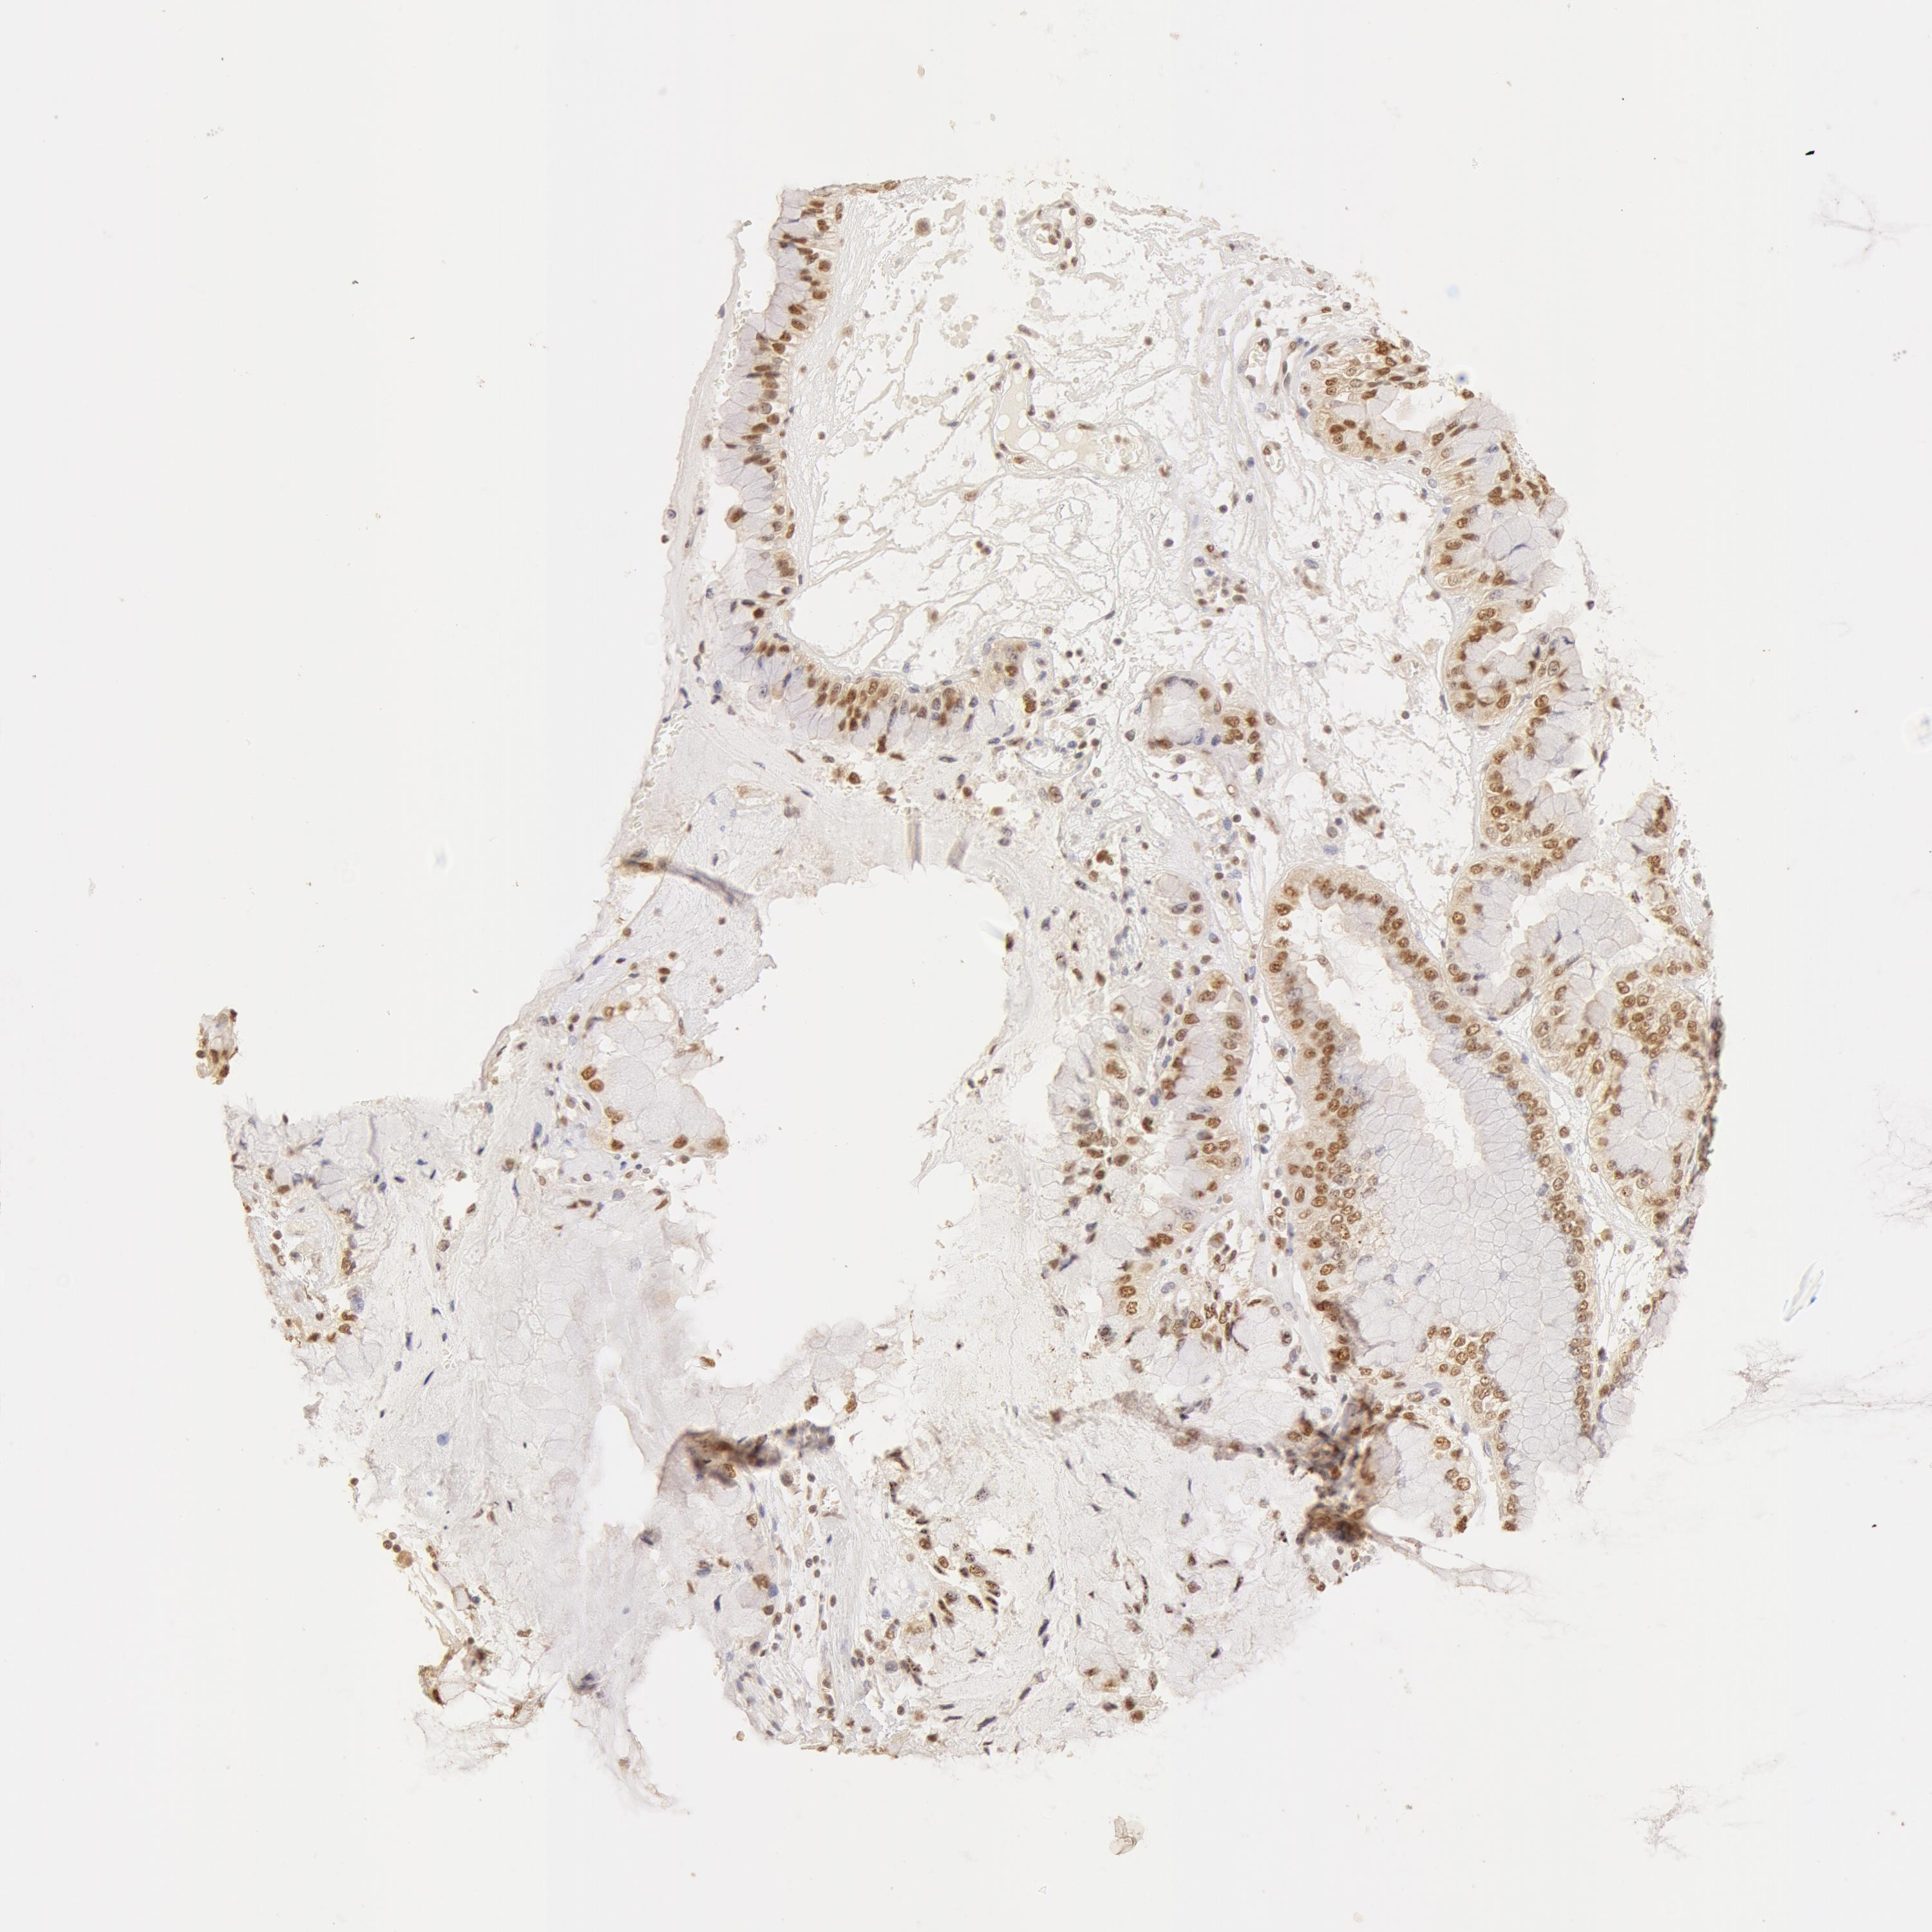

LIVER CANCER - Protein expressioni

A mouse-over function shows sample information and annotation data. Click on an image to view it in a full screen mode. Samples can be filtered based on level of antibody staining by selecting one or several of the following categories: high, medium, low and not detected. The assay and annotation is described here.

Note that samples used for immunohistochemistry by the Human Protein Atlas do not correspond to samples in the TCGA dataset.

Antibody stainingi

Antibody staining in the annotated cell types in the current human tissue is reported as not detected, low, medium, or high, based on conventional immunohistochemistry profiling in selected tissues. This score is based on the combination of the staining intensity and fraction of stained cells.

Each image is clickable and will lead to virtual microscopy that enables deeper exploration of all samples and also displays staining intensity scores, fraction scores and subcellular localization as well as patient and tissue information for each sample.

Antibody HPA042050

Antibody HPA043516

Antibody CAB001718

Staining

High

Medium

Low

Not detected

Intensity

Strong

Moderate

Weak

Negative

Quantity

>75%

75%-25%

<25%

None

Location

Nuclear

Cytoplasmic/membranous

Cytoplasmic/membranous,nuclear

Cholangiocarcinoma

Carcinoma, Hepatocellular, NOS